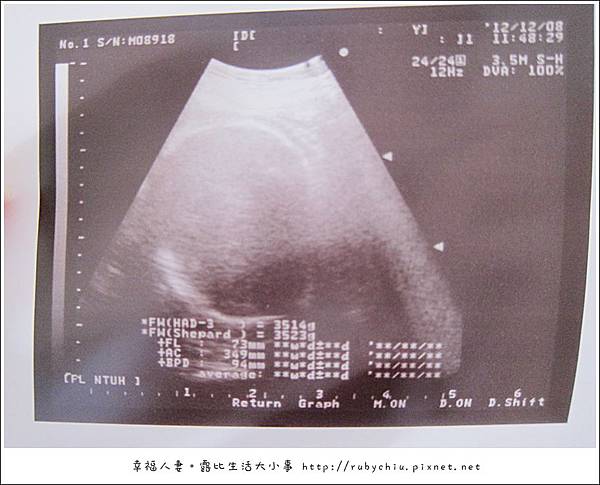

這次產檢 頭圍9.4cm 體重3500了。

曾醫生說:再不生就變巨嬰了 .. ><" 寶貝~ 下週一請準時出來啊! 拜託了。

雖然不是大頭妹妹了!但3500也算是有肉的小胖妹了!12/10 期待相見。